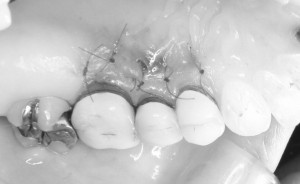

※切開

手術時の切開について

上の写真で矢印で示している部分は、手術の際に行う切開線です。

この切開線を基準として、歯ぐきの処置を次のように行います。

まず、切開線より上の歯と歯の間の歯ぐき(歯間乳頭)の部分では、歯ぐきの表面にある上皮(表面の組織)を取り除く処置を行います。これは、移動させる歯ぐきが周囲の組織となじみやすくするための準備となります。

一方で、切開線より下の部分の歯ぐきは、歯ぐきを丁寧に剥離し、歯の方向(歯冠側)へ移動できるように処置を行います。

このような処置を行うことで、歯ぐきを歯の方向へ移動させ、露出している歯の根の部分を覆うことを目指します。

※結合組織移植術

歯ぐきの移植(結合組織移植)について

歯ぐきを歯の方向へ移動できるようにフラップ(歯ぐきの組織)を形成したあと、歯ぐきが薄い部分に対して結合組織移植を行いました。

上の写真では、黄色の丸で囲っている部分が、移植した結合組織の位置になります。

このように歯ぐきの厚みを補うことで、

※手術直後

歯ぐきを移動させて縫合します

結合組織の移植を行ったあと、歯ぐきのフラップ(歯ぐきの組織)を歯の方向(歯冠側)へ移動させます。

このように歯ぐきを歯の方向へ移動させることで、露出している歯の根の部分を覆うことを目指します。

その後、移動させた歯ぐきが安定するように、吸収性の縫合糸(体内で自然に分解される糸)を使用して縫合・固定を行いました。

吸収性の縫合糸は、時間の経過とともに体内で分解されるため、状況によっては抜糸が不要となる場合もあります。ただし、経過の確認のために術後の診察を行うことが大切です。

このように歯ぐきを適切な位置に固定することで、移植した組織が安定し、治癒が進むことが期待されます。